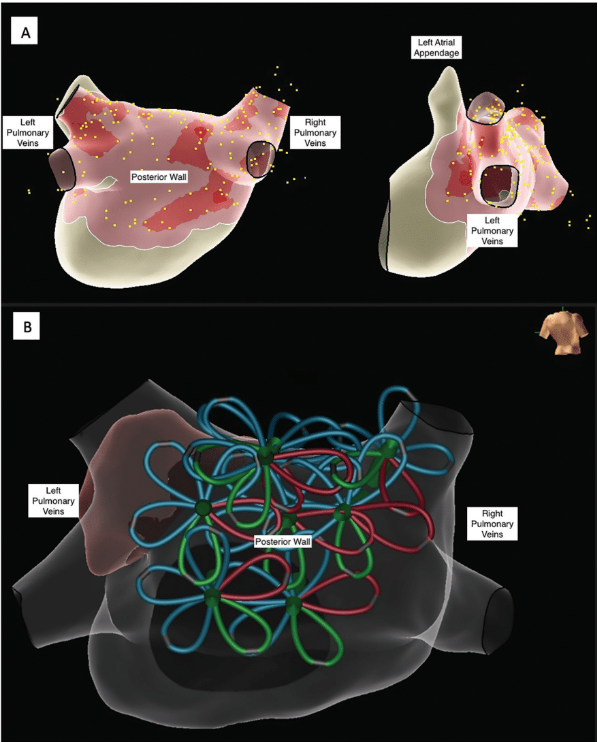

Through the transseptal sheath, detailed mapping of the LA using a multipolar catheter (Advisor HD Grid Mapping Catheter, Sensor Enabled, Abbott) was performed to define anatomy and baseline endocardial voltage, which was normal in this case. The Farapulse catheter was then advanced into the LA over a J wire, which was clearly visible with ICE in the LA. The wire was also pinned directly into the EAM to allow visualization of its tip without fluoroscopy.4 The wire was sequentially advanced into each PV and used to advance the ablation catheter in both “basket” and “flower” configurations up to the ostia and antrum of each vein, respectively, for PFA applications (Figures 1 and 2, Videos 2-4). The ICE catheter enabled undoubtful confirmation of adequate tissue contact of the splines of the ablation catheter, appropriately centered position in each vein, and dynamic surveillance of appropriate wire positioning.

After wide antrum PVI, the ablation catheter was also used in “flower” formation to deliver additional lesions in the posterior LA wall for isolation (Video 5). A total of 58 lesions (10 lesions per PV, 18 lesions on PW) were applied and tagged by projection of the ablation catheter position on the EnSite NavX (Abbott) LA map (Figure 3). LA voltage mapping was then repeated using the multielectrode mapping catheter, which confirmed successful PVI and PWI (Figure 4, Video 6). Prior to completion of the procedure, repeat ICE evaluation showed no pericardial effusion. The catheters were then removed from the body, and a combination figure-of-8 suture and vascular closure device were used to achieve hemostasis.